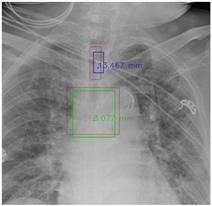

In this part, the red bboxes and points denote the GT ETT/bifurcation bboxes and the position of GT ETT tip/Carina, respectively. The blue bbox and point are the predicted ETT bbox and ETT tip, respectively. The green bbox and point are the predicted bifurcation and Carina, respectively. The light blue point is the position of the ETT tip produced by the mask branch. In the Table 23, the first row demonstrates the good results, the second row shows the medium results, and the third row presents the bad results. We noticed that if an image had a clear location of the ETT tip and the Carina, the performance would be better. Moreover, the life-supporting device might blur the location of the ETT tip and the shadow of the heart might occlude the position of the Carina as shown in the medium case. Apart from the problems mentioned above, the angle of the CXR might also degrade the performance of the proposed method, as shown in the worse results when it is applied.

Table 23.

The visualization results.